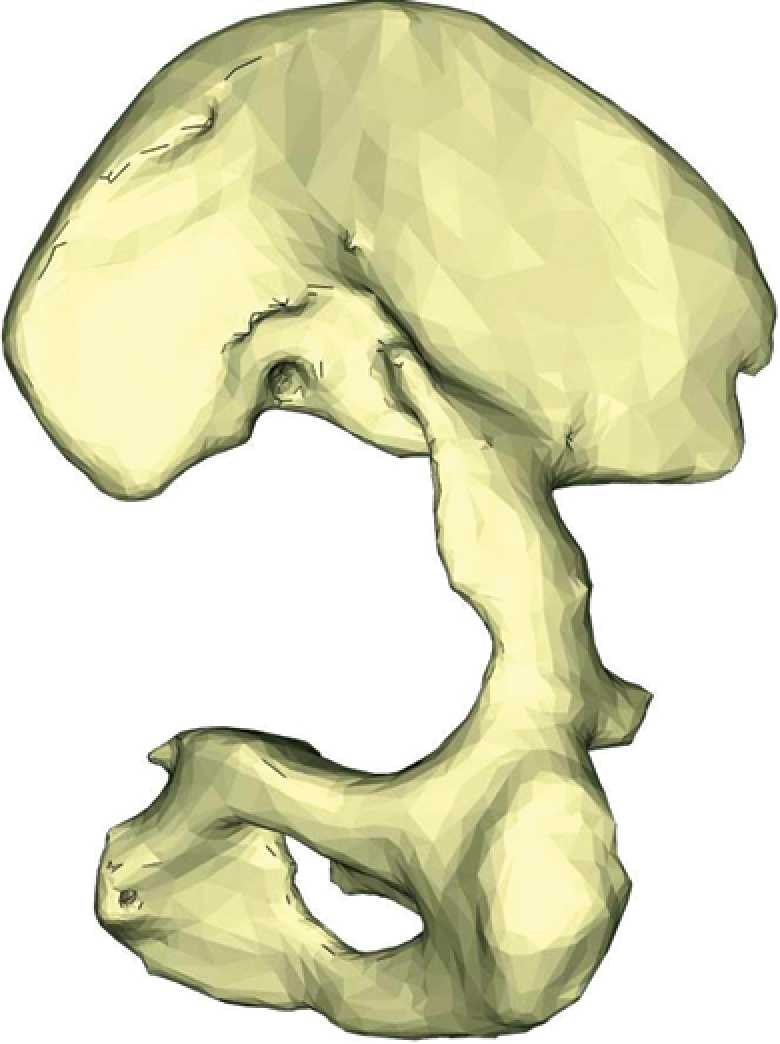

X-rays of patients with defects | ||||

Three-dimensional reconstructions of the pelvis of the same patients from the side of defect | ||||

Figure 2. Various options for acetabular reconstruction in Paprosky type 3B defect: a — lytic acetabular defect reconstructed using impaction bone grafting with implantation of a standard cemented acetabular component; b — complete anterior column defect reconstructed with an augment and a hemispherical acetabular component; c — complete medial wall defect reconstructed with augmentation and combined implantation of a hemicap cage; d — combination of complete medial wall and anterior column defects reconstructed with a Burch-Schneider antiprotrusio cage and a cemented acetabular component; e — combination of complete medial wall and posterior column defects reconstructed with a patient-specific acetabular component

Reconstruction of complete medial wall defects, as well as combined complete defects of the medial wall and anterior column, requires the use of antiprotrusio devices to ensure the stability of the acetabular component. For this combination of defects, a wide range of types and sizes of standard cages may be necessary (Figure 2 c, d). In cases of combined complete defects of the medial wall and posterior column — the most challenging in terms of biomechanical stability of the acetabular component — there is a need for a highly reliable primary fixation of the implant, which cannot always be achieved with standard revision systems (Figure 2 e).